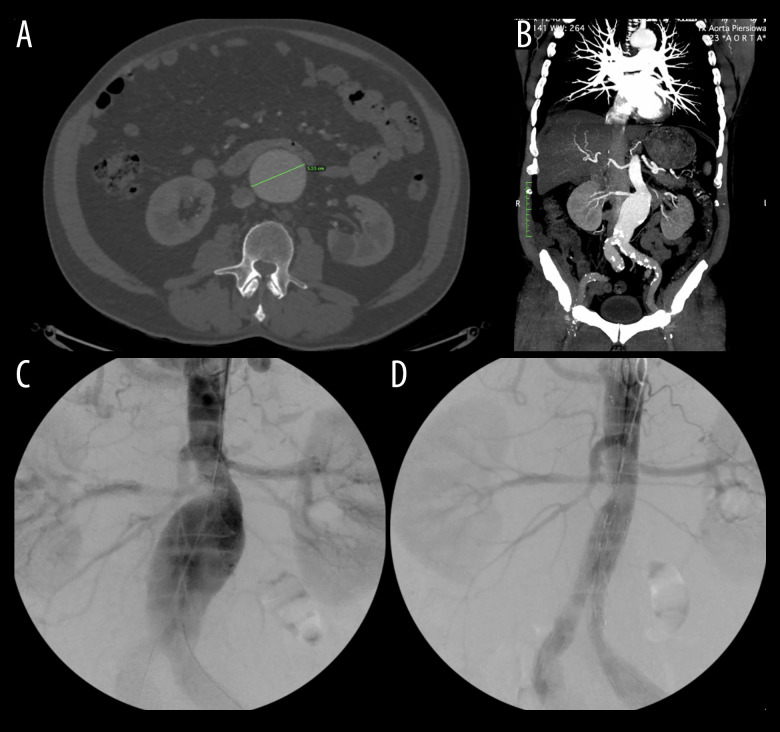

In September 2014, a 68-year-old White man presented to the emergency room with abdominal bloating. While on holiday, where he was admitted to a hospital due to a urinary tract infection, during which he had a CT scan that revealed an incidental AAA. Subsequently, upon physical examination in our hospital, an abdominal palpable mass was found with no other unusual findings or symptoms. CT showed a 55-mm-diameter AAA (Figure 1). He did not smoke and drank alcohol occasionally. He had no significant medical history and denied connective tissue disorder and chronic diseases in the family, including family history of AAA. Additionally, he reported that both of his parents died of stroke at the age of 70. He was admitted to the hospital for further investigation, and the following year, a Cook Fenestrated 28/24-mm stent was placed successfully and without complications (Figure 1).

Figure 1.

Non-contrast-enhanced CT (A) and contrast-enhanced CT (B) of the abdominal aortic aneurysm (AAA) measuring 55 mm. The same AAA in 2015, before the EVAR procedure (C) and after it (D). CT – computed tomography.